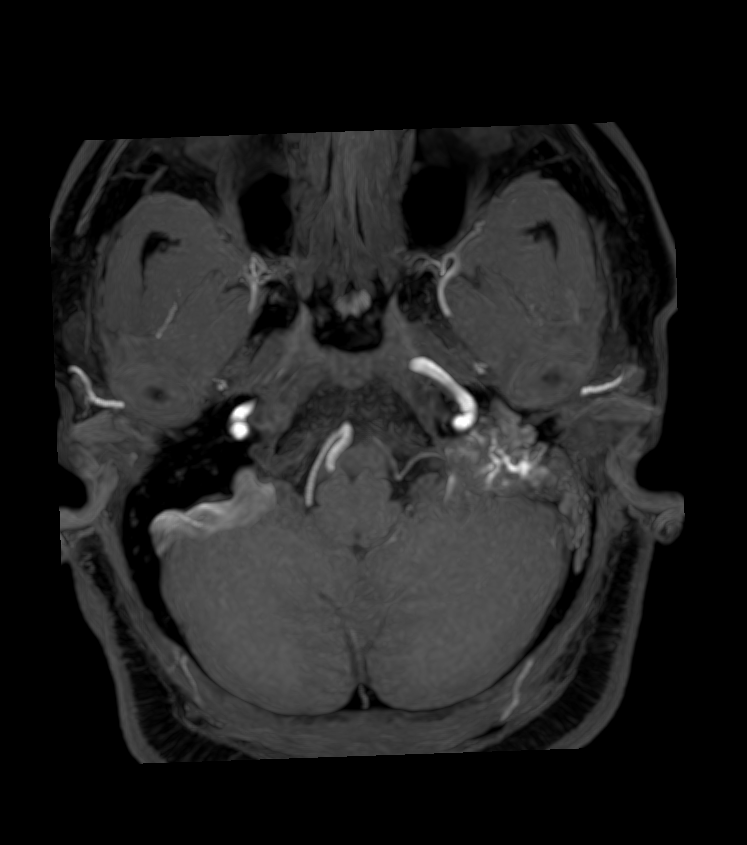

- 40-year-old patient presented with hearing loss and facial palsy.

- MRI showed a lesion in the left jugular foramen and petromastoid bone with evidence of vascularity on T2-weighted imaging (i.e., flow voids) and time-of-flight angiography. Ga-DOTATATE PET showed avid tracer uptake as expected in a paraganglioma.